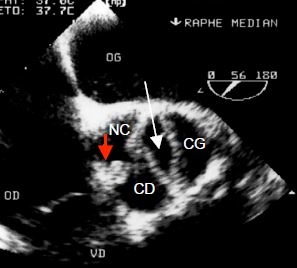

- CIV infundibulaire ou supracristale (5% des cas) (Vidéo et Figure 15.31): elle se situe juste en dessous de la valve pulmonaire et communique avec la chambre de chasse gauche sous la valve aortique; ce voisinage induit fréquemment le prolapsus d'un ou de deux feuillets de la valve aortique (coronaire droit et plus rarement non-coronaire), ce qui conduit à une insuffisance aortique.

Vidéo: CIV supracristale, située entre les chambres de chasse gauche et droite; présence d'une minime insuffisance aortique.

Figure 15.31 : Image de CIV infundibulaire ou supracristale, située sous la valve aortique ; le passage est démontré par le flux Doppler couleur. Cette CIV fait communiquer les deux chambres de chasse entre elles.